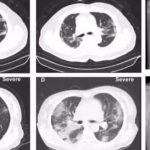

Ահա թե ինչ է կատարվում երբ վարակվում եք COVID19 – ով

COVID19 մեծ աղետ է ամբողջ աշխարհի համար։ COVID19 տարածման 7֊8 (իսկ Հայաստանում 3,5) ամիսների ընթացքում անընդհատ ի հայտ են գալիս մի շարք նոր կլինիկական...